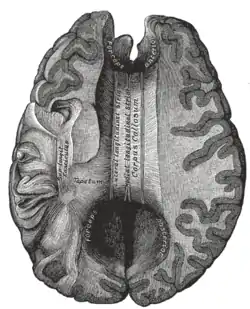

Corpus callosum from above, front part at the top of the image.

The corpus callosum (Latin for "tough body"), also callosal commissure, is a wide, thick nerve tract, consisting of a flat bundle of commissural fibers, beneath the cerebral cortex in the brain. The corpus callosum is only found in placental mammals.[1] It spans part of the longitudinal fissure, connecting the left and right cerebral hemispheres, enabling communication between them. It is the largest white matter structure in the human brain, about ten centimetres in length and consisting of 200300 million axonal projections.[2][3]